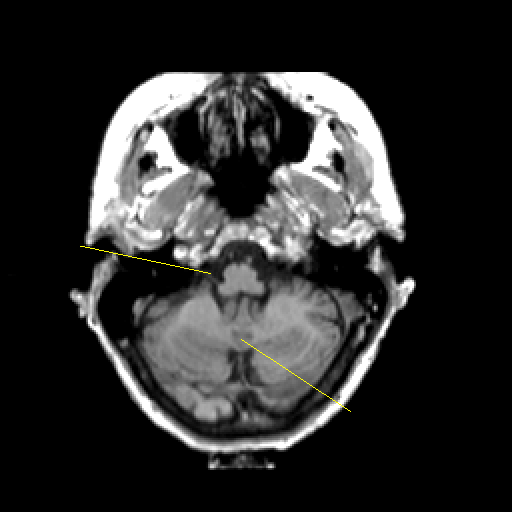

T1-weighted structural MR: Slice 11

Slice 11

Pointers

Labeled